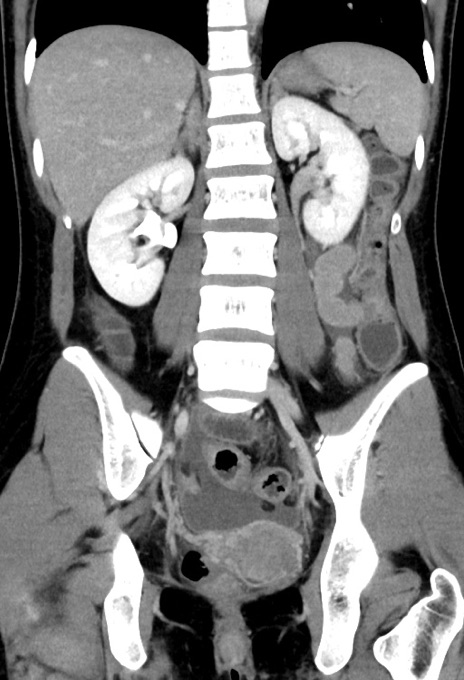

症例17(冠状断像)

【症例】20歳代女性

【主訴】嘔吐、下腹部痛

【現病歴】昨日夕食後に嘔吐し下腹部痛が出現。本日になっても嘔吐持続し改善しないため来院。

【身体所見】意識清明、BT 37.2℃、BP 108/67mmHg、腹部:平坦、やや硬、下腹部正中から右にかけて圧痛あり、反跳痛軽度あり、tapping pain(+)。

【データ】WBC 13600、CRP 14.94